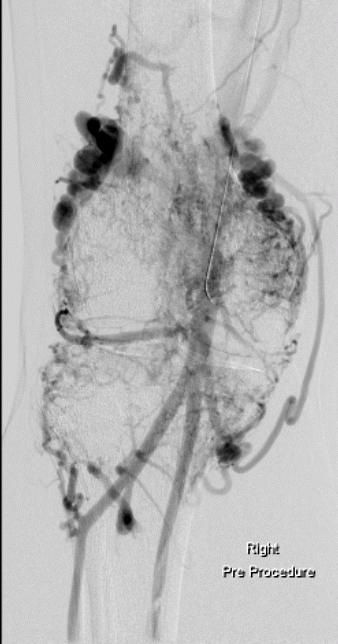

Onyx 胶在肢体血管畸形方面的应用

14岁男孩,静止情况下前臂不适,手运动后疼痛

两年前栓塞治疗前